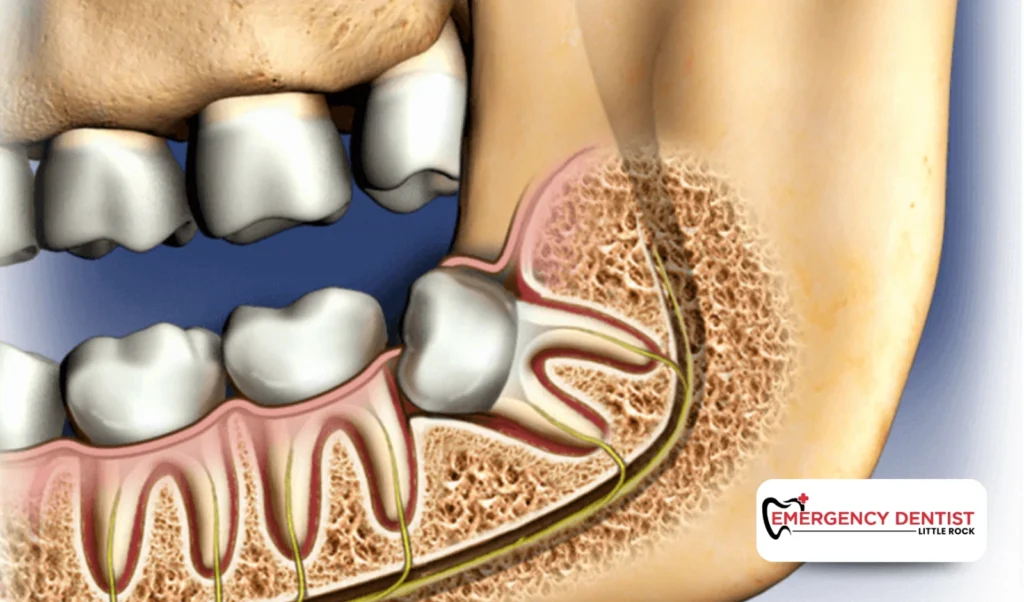

A surgical extraction is required when the tooth is partially erupted, broken, or located beneath the gums. This is common with an impacted wisdom tooth.

Surgical extraction may involve:

• Lifting gum tissue

• Removing small amounts of bone

• Dividing the tooth into smaller sections

An impacted wisdom tooth does not fully emerge through the gums. It may grow sideways or press against nearby teeth. These situations often require oral surgery techniques and more careful planning.